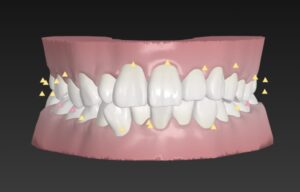

🔶初診時🔶

正面

歯並びガタガタの

そうせい を気にして来院

マウスピース矯正希望で

インビザラインではなく

インビザラインのジェネリック

クリアコレクトを希望

そうせい は

アゴのサイズに比べて歯が大きすぎるので

歯が並ばずガタガタに

この歯並びは

特に下の前歯はガタガタしすぎて

歯磨き🪥が出来ず

虫歯や歯周病で歯を失うリスクが

治療開始にあたり

まずは歯並びをお口のスキャナー

トリウスでスキャン

今回は小臼歯の抜歯は不用

歯と歯の間を0.2〜0.4ミリ削り

歯を小さくして

出来たスキマ分

歯をキレイに整列

🔶アフター🔶